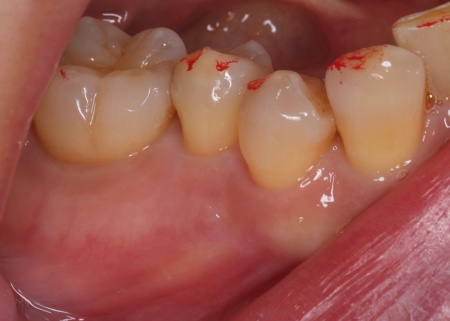

50代女性 治療が不十分だった歯に再度根管治療を施しジルコニアクラウンで修復した症例

「欠けた歯を治して白い歯を入れたい」とご相談いただきました。

拝見したところ、左上の小臼歯が欠けていました。

レントゲンを撮り詳しく確認したところ、過去に根管治療が施されていたものの、根の中に薬がしっかりと詰められておらず治療が不十分な状態でした。そのため、根管から歯根を覆う歯根膜が細菌感染して炎症を起こす慢性歯根膜炎が生じています。

このまま放置すると細菌感染がさらに進行し、歯根周囲の骨が破壊されたり膿んだりして最終的に歯を失うおそれがあるため、早急な治療が必要と診断しました。